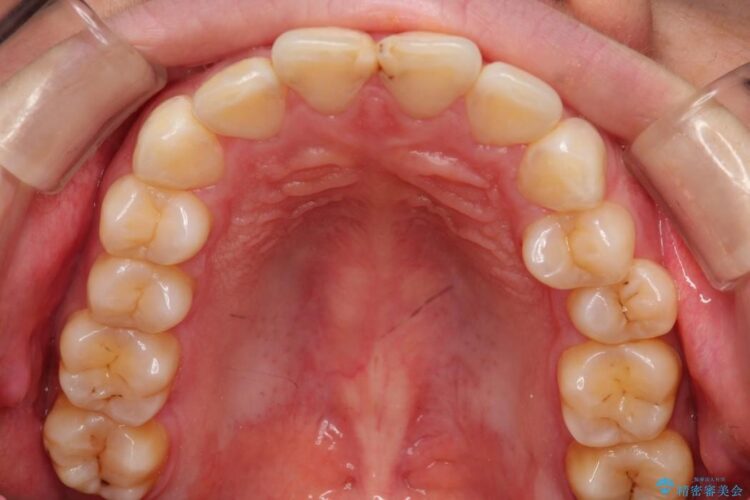

【20代女性】出っ歯の矯正 治療例

治療費の安い矯正治療を希望されていたため、メタルのワイヤー装置にて治療する計画にしました。また、歯みがきが苦手だったため、矯正治療をする前に徹底的にブラッシング指導を行いました。

出ている歯を引っ込めるためのスペースを作るため、上下左右の小臼歯を抜歯し、ワイヤー矯正を行いました。治療後は、口元がスッキリとしたことで患者様にも喜んでいいただきました。